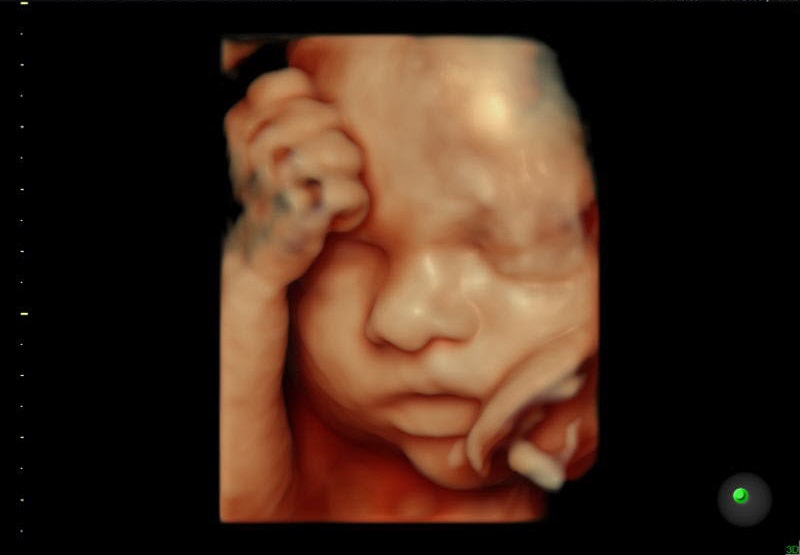

Ecografía de un bebé en el vientre materno.